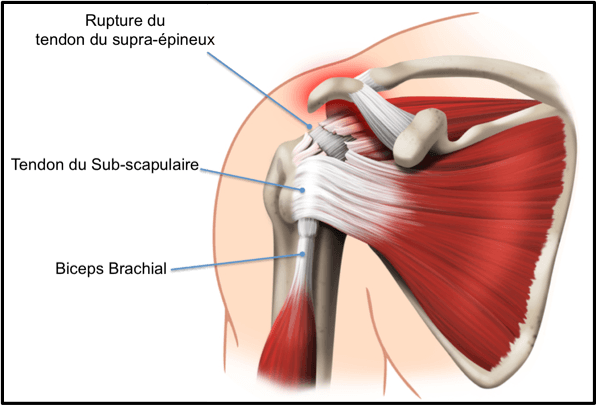

تعتبر أوتار الكتف الدوارة من أهم المكونات التشريحية في جسم الإنسان، فهي تساهم في استقرار مفصل الكتف وتسمح بتحريك الذراع في جميع الاتجاهات، وتشمل هذه الأوتار العضلات الأربعة الأساسية: العضلة فوق الشوكة (Supraspinatus)، العضلة تحت الشوكة (Infraspinatus)، العضلة المدورة الصغيرة (Teres Minor)، والعضلة تحت الكتف (Subscapularis)، وهذه الأوتار تعمل بتناسق تام للحفاظ على قوة ومرونة الكتف، ومع ذلك فهي معرضة للإصابة بعدة مشاكل، ومن أهمها اختناق الأوتار الدوارة وهو ما يمكن أن يؤدي على المدى الطويل إلى تمزق جزئي أو كامل للأوتار، وهذا الأمر يؤثر بشكل مباشر على وظيفة الكتف والحياة اليومية للمصاب؛ وخلال السطور القادمة سنقوم بشرح كافة التفاصيل التي تخص سؤال هل اختناق الاوتار الدوارة يؤدي الي القطع ؟ والتعرف علي أفضل دكتور لعلاج اوتار الكتف.

يعد الاختناق المزمن للأوتار الدوارة من العوامل الرئيسة المؤدية إلى تمزق جزئي أو كامل للأوتار، فالتعرض المستمر للاحتكاك يضعف ألياف الأوتار تدريجيًا، وتظهر الدراسات الطبية أن الأشخاص الذين يعانون من اختناق الأوتار لفترات طويلة دون علاج يواجهون خطر تمزق بنسبة تتراوح بين 30% و50% على المدى الطويل، وغالبًا ما يكون التمزق في أوتار العضلة فوق الشوكة (Supraspinatus) لأنها تقع مباشرة تحت منطقة الضغط، ويبدأ التمزق عادة كتمزق صغير جزئي ثم يتطور تدريجيًا إلى قطع كامل، مما يقلل قدرة الكتف على رفع الذراع وحمل الأوزان، ويصاحبه الألم المستمر وضعف العضلات.

العلاج الجراحي

يطبق عندما يفشل العلاج المحافظ أو عند وجود تمزق كبير ويشمل:

- تنظيف الأوتار وإزالة النتوءات العظمية: لتقليل الاحتكاك على الأوتار.

- إصلاح التمزق الجزئي أو الكامل: سواء بالجراحة المفتوحة أو المنظار الجراحي.